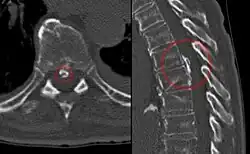

Magnetic resonance imaging (MRI) is the preferred modality for the evaluation of back pain and visualization of bone, soft tissue, nerves and ligaments. X-rays are a less costly initial option offered to patients with a low clinical suspicion of infection or malignancy, and they are combined with laboratory studies for interpretation.

Imaging is not warranted for most patients with acute back pain. Without signs and symptoms indicating a serious underlying condition, imaging does not improve clinical outcomes in these patients. Four to six weeks of treatment is appropriate before consideration of imaging studies. If a serious condition is suspected, MRI is usually most appropriate. Computed tomography is an alternative if MRI is contraindicated or unavailable.[40] In cases of acute back pain, MRI is recommended for those with major risk factors or clinical suspicion of cancer, spinal infection or severe progressive neurological deficits.[41] For patients with subacute to chronic back pain, MRI is recommended if minor risk factors exist for cancer, ankylosing spondylitis or vertebral compression fracture, or if significant trauma or symptomatic spinal stenosis is present.[41]